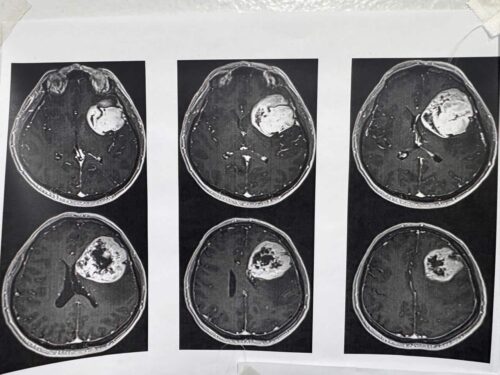

Para Determinar La Realización De Este Procedimiento Y Conocer El Orígen De Los Síntomas, Explicó, El Equipo Médico Del Instituto Le Realizó Al Derechohabiente Estudios De Tomografía Y Resonancia Magnética.

“Se Realizó Tomografía De Cráneo Y, Ante Los Hallazgos, Se Le Practicó Una Resonancia Magnética; Posteriormente, Se Le Detectó Un Tumor De Características Malignas En La Región Frontal Premotora Izquierda”, Detalló.